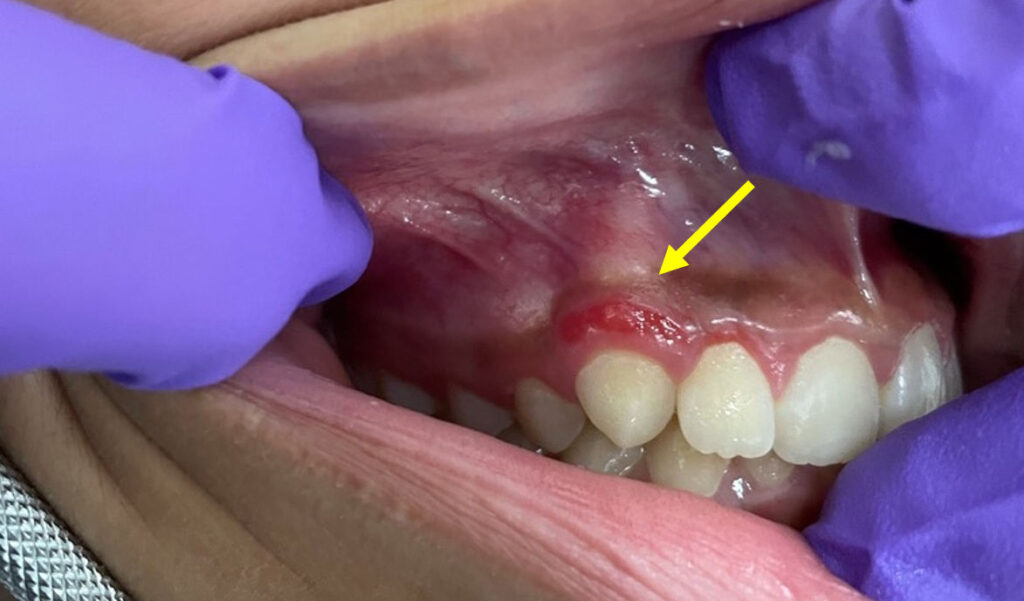

39-year-old woman with mandibular lesion

A 39-year-old woman with a lesion on the right side of the posterior mandible.